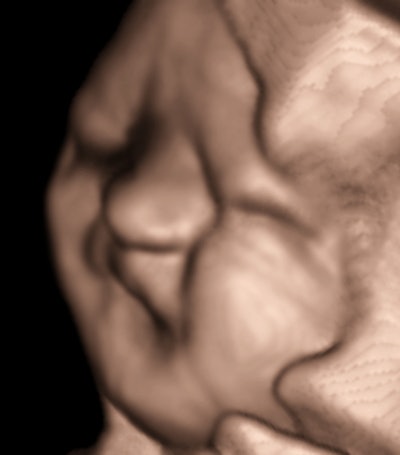

All images courtesy of Dr. Jason Birnholz.

There are high-velocity spicules in the tracing. We have tended to think of these as microturbulence events, signaling the presence of surfactants in ejected lung fluid. This is unusual at the current gestational age in a male fetus, except when there has been repeated stress promoting lung maturation.We hit the panic button when we observed a lot of exaggerated head and torso movements (like aversive behavior) with a lot of mouth and tongue activity. I will leave it to you to decide what to make of fetal expression during one of the movement episodes.

Pulmonary maturation was confirmed, the patient was delivered, and the outcome was fine. Everything might have been equally fine with simple observation, but no one, including the prospective parent, thought the risk would have been warranted, even though the clues to problems were in the subjective, if not flaky, area of behavior.